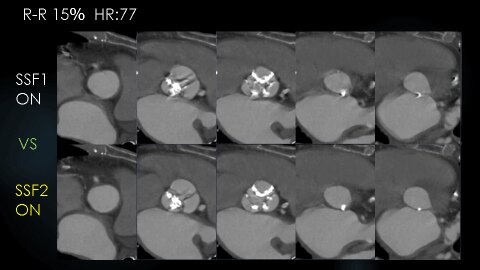

下図はHR77の高心拍の症例で、SSF2.0と第一世代のSSF1.0での駆出期の画像の比較です。SSF1.0ではどの位相でもモーションアーチファクトが残存しています。 SSF2.0導入後は、どの位相においても(図1)、またどの断面においても(図2)、モーションアーチファクトが抑制された画像が得られていました。

図1 Annulus断面の比較

図2 STJからLVOT断面までの比較